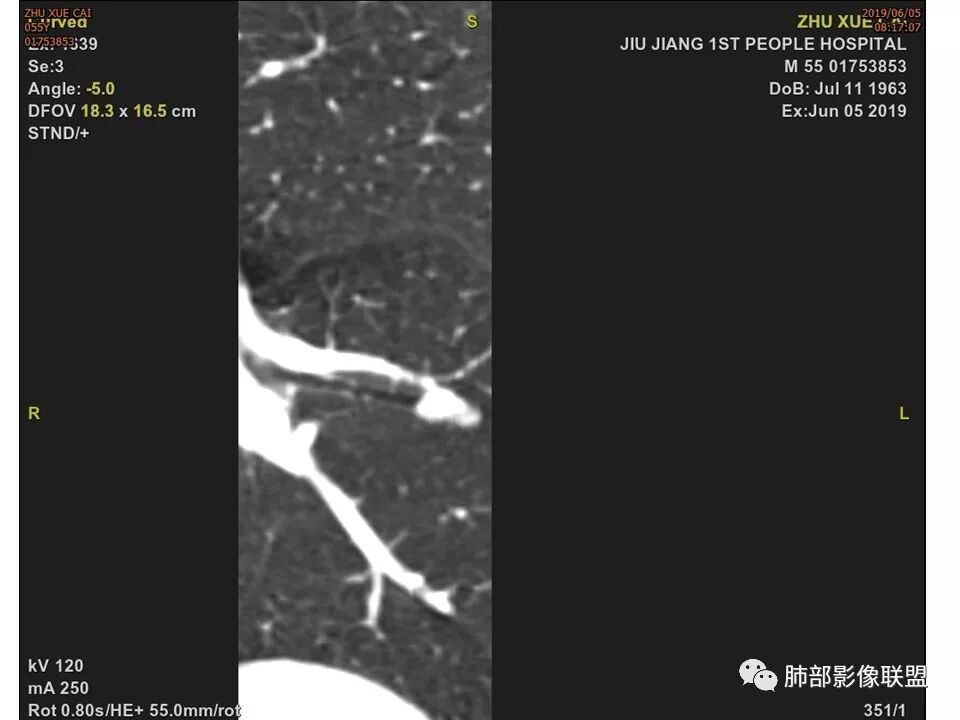

左肺下叶前内基底段结节 深分叶和脐凹 表面部分膨隆 部分收缩 支气管截断 轻度强化 中央有坏死 考虑鳞癌 鉴别炎性结节

中年男性,支气管门口截断、邻近支气管未见管壁增厚,分叶明显,边缘彭隆,内见小坏死灶,周围未见GGO,考虑周围性鳞癌,鉴别炎性肉芽肿。

病灶多结节融合,有分叶,也支气管截断,有细小血管连接,考虑恶性结节,周围型肺癌。

左肺下叶前内基底段结节,轮廓凹凸不平,局部边缘平直,密度不均,近段支气管阻塞,增强前后CT值无明显变化,考虑肉芽肿,结核?腺癌代排

左肺下叶前基底段结节,病灶边缘分叶,边缘平直,u型征,可见气管截断,增强可见病灶边缘血管,平扫ct值低,轻度强化。考虑良性病变。

不是假象,是真的堵了,我工作站薄层做了气管曲面重建,仿真内窥镜也显示堵了

也咨询了病理科老师,肺软骨瘤来源于支气管透明软骨,理论上可以从黏膜下,突向支气管腔内生长,对支气管造成压迫性的阻塞。影像上和软骨瘤样错构瘤没法区分